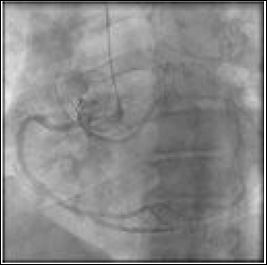

Cardiac catheterization was done given the patient’s high risk for Coronary Artery Disease (CAD) and chest pain complaints. The differential diagnosis would include occlusive coronary artery disease, Prinzmetal angina, microvascular coronary artery disease, coronary syndrome X, spontaneous coronary artery dissection, anomalous coronary artery with interarterial course. The coronary angiogram revealed an anatomic anomaly of the left main coronary artery (Figure 1). There was no obstructive CAD found. Coronary Computed Tomography Angiography (CTA) was subsequently ordered to further assess the anatomy and origin of the coronary arteries. CTA revealed a single coronary ostium with common origin of the right and left coronary arteries arising from the right sinus of Valsalva. The left coronary artery coursing posteriorly between the aortic root and left atrium, without an abrupt acute angle, intramural course, or fish-mouth ovoid appearance of the ostium (Figure 2).

Figure 1: Coronary Angiography: LAO 30 degrees. Single coronary ostium arising from the right coronary cusp. Anomalous left main coronary artery arising from the right coronary artery.